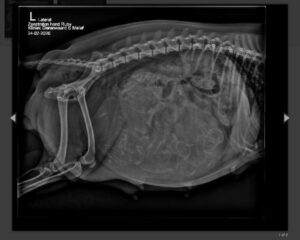

De laatste loodjes voor Ruby een buikje vol!

24 februari 2026